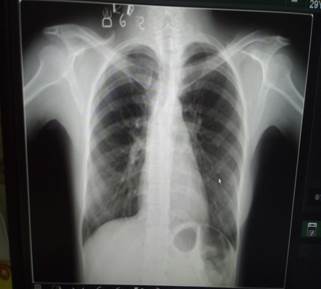

En la radiografía de tórax digital, vista posteroanterior (PA) (Figura 1), realizada al ingreso, no se observó neumotórax.